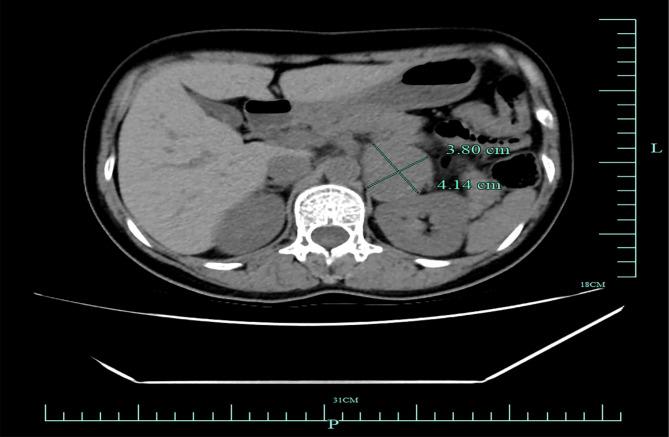

一名37岁女性计划在全身麻醉下行扁桃体切除术和腭咽成形术,诱导后发生恶性心血管事件,主要表现为心率和血压急剧升高,最终导致心脏骤停及继发性长QT综合征的发生。根据围手术期临床表现、血浆和尿儿茶酚胺测定、术后双侧肾上腺计算机断层扫描结果及手术病理结果,该患者被诊断为未被诊断出的嗜铬细胞瘤。